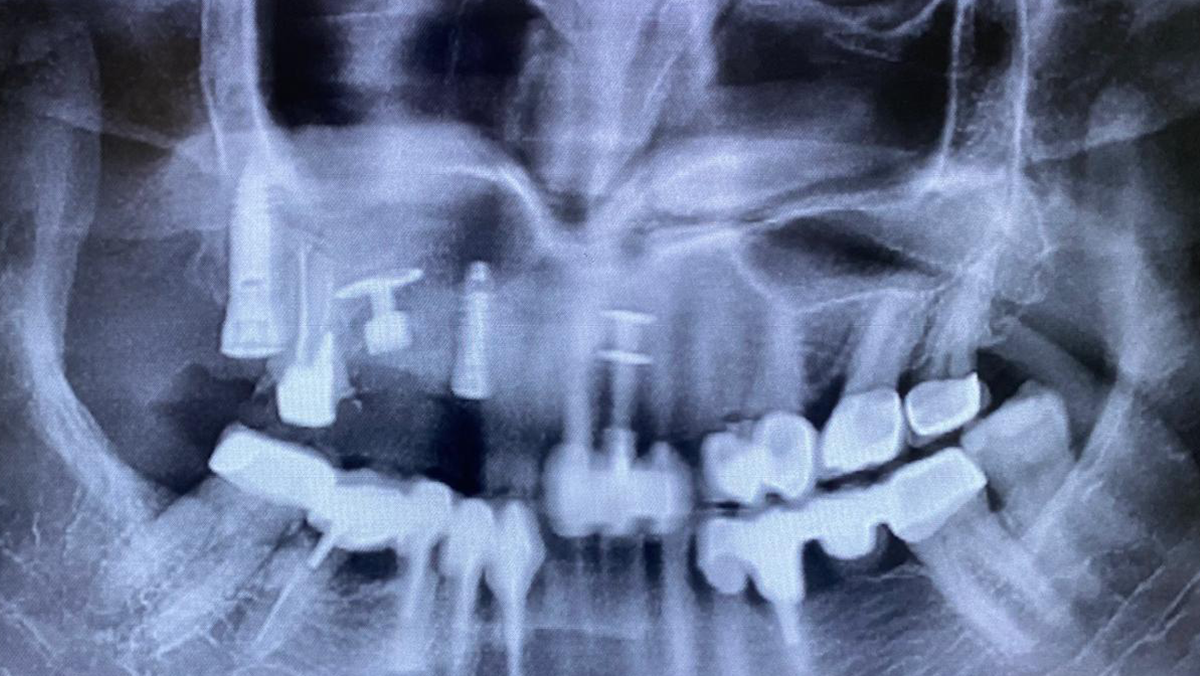

une chirurgie en direct commentée par le Dr Gérard Scortecci, réalisée dans le secteur postérieur maxillaire droit

Implants Victory® posés lors de cette chirurgie

Le bridge anticipé est une prothèse provisoire conçue à l’avance, avant la chirurgie, grâce à la planification numérique et à l’aide de l’intelligence artificielle.

L’IA analyse les données du patient pour optimiser la forme, l’ajustement et les points d’appui du bridge.

Mots du docteur Scortecci : «Ce bridge a pu être installé immédiatement à la fin de la chirurgie, offrant un résultat esthétique et fonctionnel instantané.“

APRÈS